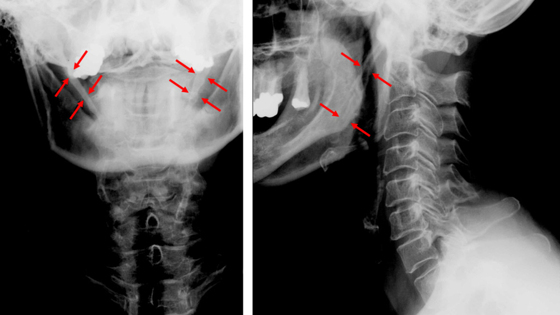

На КТ было обнаружено аномальное удлинение шиловидных отростков — костных выступов у основания черепа. В норме их длина не превышает 3 сантиметров. А у ребенка они выросли до 6 сантиметров с каждой стороны. Это заболевание обычно встречается только у взрослых пациентов в возрасте 30–50 лет. Отростки удлиняются за счет окостенения шилоподъязычной связки. Точные причины этого процесса неизвестны. Но иногда эта связка может начать накапливать кальций на фоне множественных инфекционных заболеваний ротоглотки.

Безопасно удалить эти длинные части, не повредив саму шею, было крайне сложно. Врачи использовали доступ через естественную складку на шее. Во время операции им удалось отделить отростки от сосудисто-нервных пучков и удалить их практически без кровопотери. Боль при поворотах головы перестала беспокоить мальчика сразу же после операции.